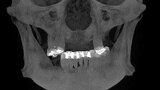

Implantacja z wykorzystaniem szablonu nawigacyjnego 3D